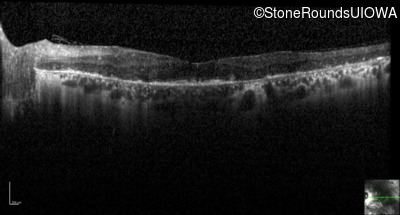

Infrared Fundus Photograph - Right - 20/25

Exemplar